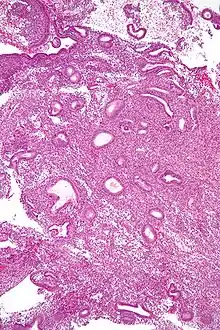

A biópsia endometrial é um procedimento médico que envolve a colecta de uma amostra de tecido do revestimento do útero. O tecido é posteriormente submetido a uma avaliação histológica que auxilia o médico na formação de um diagnóstico.